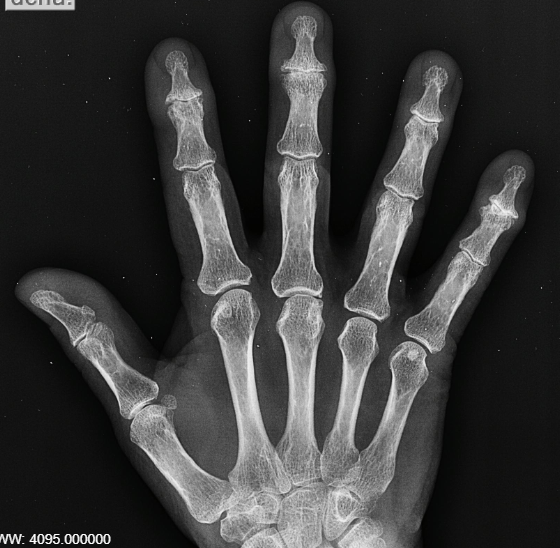

Las lesiones óseas de las manos son un tipo de daño que afecta a los huesos de la mano. Pueden ser causadas por una variedad de factores, como accidentes, caídas, golpes o movimientos repetitivos.

Los tipos más comunes de lesiones óseas de las manos son:

Fracturas: Una fractura es una rotura en el hueso. Las fracturas de las manos pueden ser causadas por un golpe directo, una caída o un movimiento repetitivo.

Luxaciones: Una luxación es una dislocación de una articulación. Las luxaciones de las manos pueden ser causadas por un golpe directo o un movimiento repentino.

Artritis (inflamatoria o degenerativa): Esto pueden ser causadas por un movimiento repetitivo y un esfuerzo excesivo o por causas inflamatorias o familiares de diferente índole.

![]() |